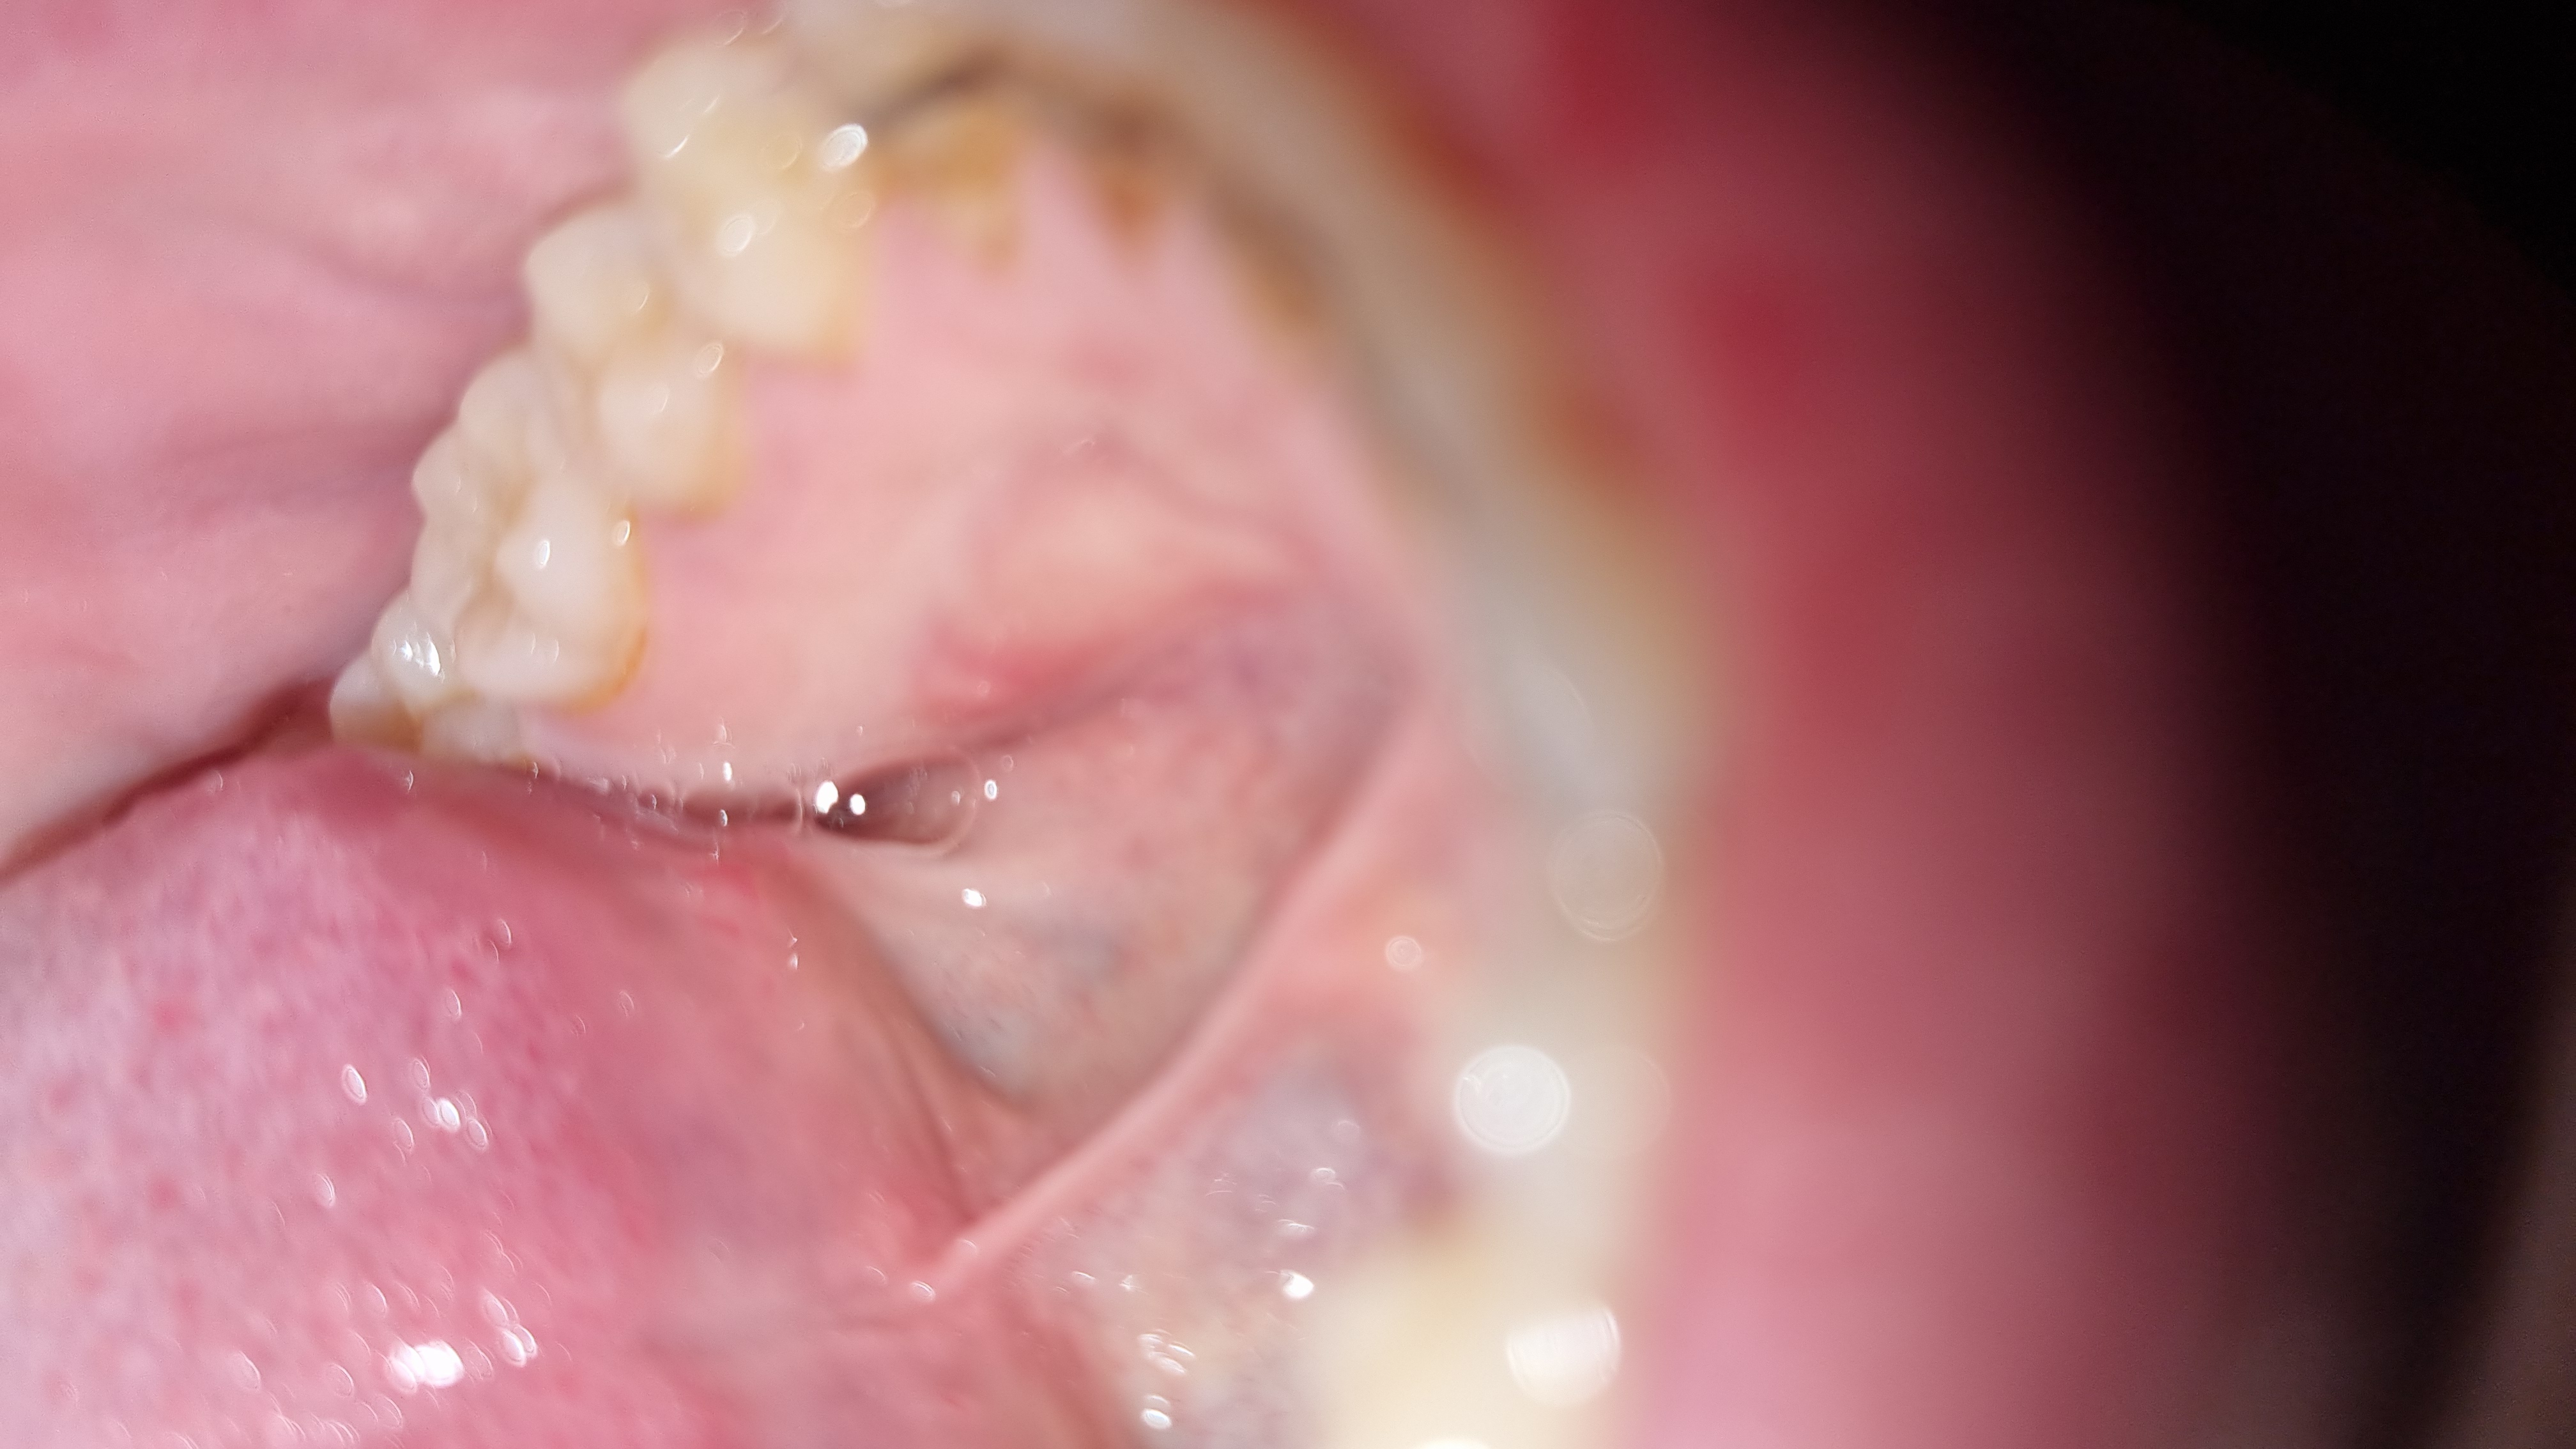

Buongiorno, Sono una ragazza di 25 anni. Da circa un mese ho notato con la lingua un rigonfiamento nel palato inferiore. Appare bianco e arrossato nella zona circostante. Non è dolente se non al tatto è ha una consistenza dura. Non so cosa possa essere e se debba preoccuparmi. Non è cresciuta in questo periodo di tempo. È spuntata da un giorno all'altro.

Assolutamente nulla di preoccuante. Una esostosi ch tutti hanno - se ne è accorta solo ora ma c'è sempre stata. Se qualcosa cambia in un paio di settimane si faccia visitare..

Gentilissima utente le foto non sono affidabili, occorre visita odontoiatrica.